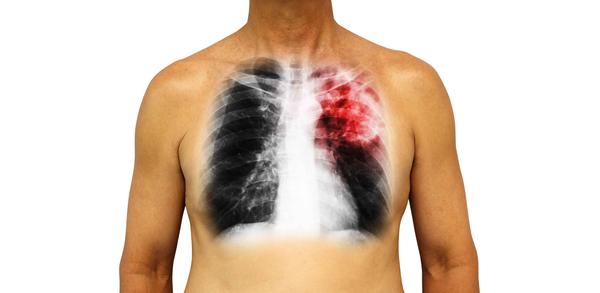

目前患有肺癌的人数很高 , 这不仅威胁着患者的生命 , 也给经济带来巨大压力 , 因此也让很多人对这种疾病提高了重视 。

想要避免这种疾病的出现 , 就要了解这种疾病的发生原因 , 尽可能的使自己远离这些高危性因素 。

那么肺癌人数疯狂上涨的原因是什么呢?以下4个诱因很容易被人们所忽视 , 再不加以重视可能就会诱发肺癌 。